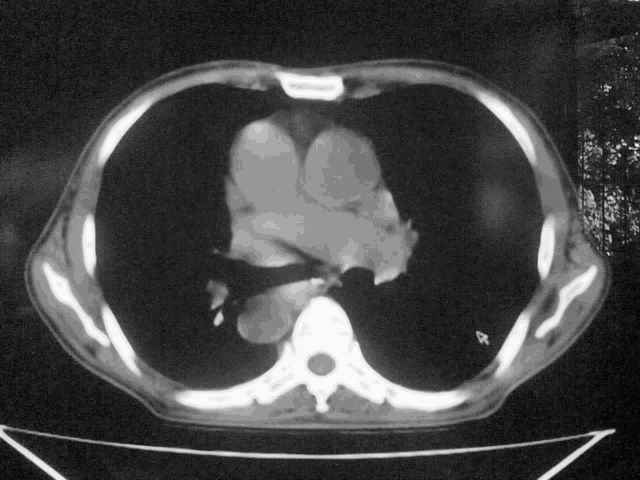

我这个考考大家眼力,看看是升结肠ca还是降结肠ca

好象是横结肠占位肝转移,胰头占位?【伙计,您的片也真够意思】

横结肠占位肝转移

伪影太多,考虑降结肠癌伴肝转移,胆囊炎

伪影太多,考虑升结肠癌伴肝转移,胆囊炎

好象是横结肠占位肝转移,胰头占位?

考虑升结肠癌伴肝转移;胆囊炎。

好象是横结肠占位肝转移.

结肠占位并肝及腹膜后淋巴结转移。

明确考眼力!考虑降结肠癌伴肝转移可能性。

考虑升结肠癌伴肝转移;胆囊炎